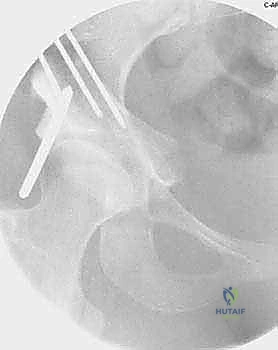

2. سلسلة قطع العظام (The 5 Osteotomies)

يكمن سر نجاح جراحة PAO في إجراء خمسة قطوع عظمية منفصلة حول الحُق، لتحريره بالكامل عن باقي الحوض، مع ترك العمود الخلفي سليماً كدعامة أساسية.

القطع الأول: القطع الإسكي غير المكتمل (Incomplete Ischial Osteotomy)

باستخدام إزميل خاص ذو زاوية (Angled Osteotome)، يتم إجراء قطع في عظم الإسك أسفل الحُق مباشرة (في الأخدود تحت الحُقي). يتم هذا القطع بتوجيه الأشعة السينية (Fluoroscopy) لضمان عدم اختراق المفصل. يحرص الدكتور هطيف على إبعاد العصب الوركي والأوعية السدادية بأمان تام.